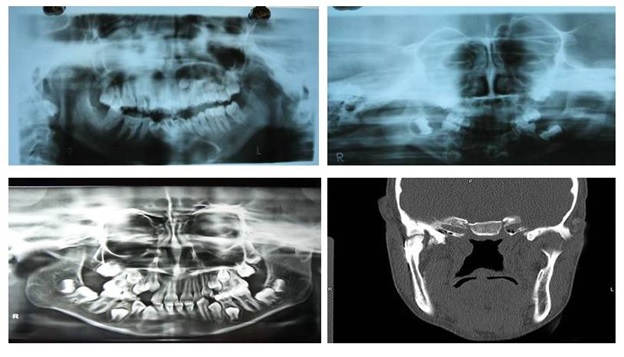

Total 10 patients with Temporomandibular Joint (TMJ) ankylosis reporting to the outpatient department of Oral and Maxillofacial Surgery, Maharaja Ganga Singh Dental College and Research Centre, Sri ganganagar, Rajasthan, India were included irrespective of age, sex, caste and socioeconomical status. Diagnosis of TMJ ankylosis was based on the basis of clinical assessment as Maximum inter-incisal Mouth Opening (MMO) [Table/Fig-1] and other cardinal signs of ankylosis [1] followed by radiographic assessment using Postero-anterior (PA) mandible view, Orthopantomogram (OPG), lateral oblique view and CT scan which showed various degrees of condylar involvement with condyles varying from normal size to a large spherical mass involving the condylar process as well as the coronoid process [Table/Fig-2].

Pre-operative maximum mouth opening.

3D CT scan showing ankylotic mass.